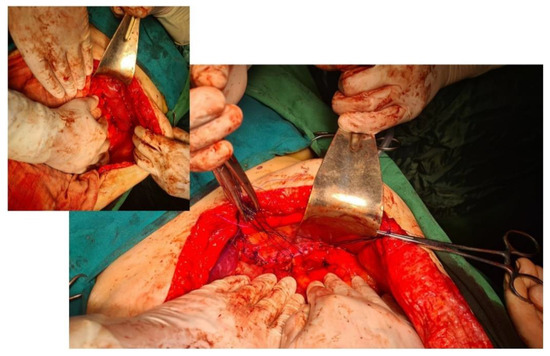

Approach options are the thoracic, abdominal, or combined thoraco-abdominal approach, classic or minimally invasive [22]. The advantages of the thoracic approach over the abdominal approach are direct visualization of the hernial contents and non-negative intrapleural pressure, which facilitates reduction. Through the thoracic approach, adhesions between herniated viscera and the lung or pleura can be safely dissected, although few intrapleural adhesions have been found in previous reports. On the other hand, the thoracic approach in its classic version has the disadvantage of a much more “aggressive” technique for the patient; it forces selective intubation, a surgical gesture limited by the intercostal access, an often much more complex resuscitation, and a difficult, long recovery. In contrast, the advantage of the abdominal approach is the easier recognition and management of possible strangulated bowel loops or concomitant abnormalities of the abdominal viscera [23]. The abdominal approach is more commonly used than the thoracic approach and may be more appropriate in complicated cases with strangulation, ischemia, or visceral abnormalities. Minimally invasive thoracoscopic, laparoscopic, or robotic surgical interventions have slowly become the procedures of choice and are increasingly used on both sides of the diaphragm [24] due to their well-known advantages (Figure 4). The presence of strangulation, volvulation, and perforation are formal contraindications to a minimally invasive technique, but here it must be judged on a case-by-case basis [25,26,27].

Figure 4. Intraoperative aspect of laparoscopic surgery for Bochdalek diaphragmatic hernia—the diaphragmatic defect of about 18 cm is highlighted. In the smaller image is the final appearance after primary suture of the defect and reinforcement with biological mesh.